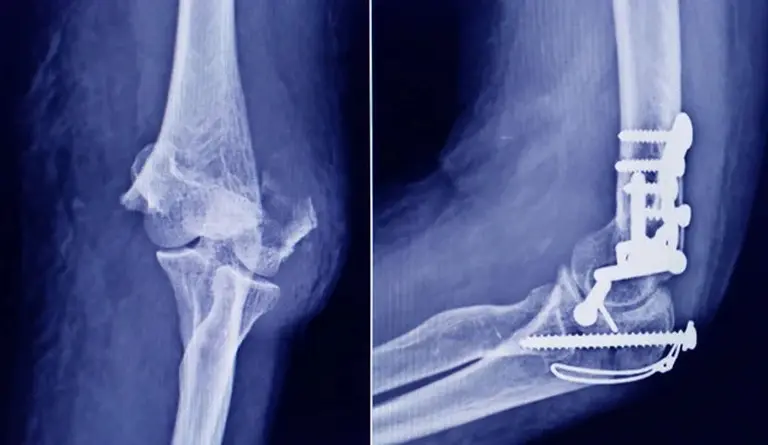

La Administración Nacional de Medicamentos, Alimentos y Tecnología Médica (ANMAT) advirtió a la población por un tornillo utilizado en cirugías traumatológicas debido a que es falso, por lo que su uso representa riesgo para la salud del paciente al que se lo implante.

Se trata de un tornillo utilizado en cirugías traumatológicas que fue detectado durante una inspección de control de mercado realizada en una ortopedia ubicada en la ciudad de San Miguel de Tucumán.

Dicho tornillo es producido por la firma Stryker Corporation, que se encuentra registrada ante ANMAT bajo el PM 594-139. Luego de la inspección, se exhibió la muestra recolectada ante la responsable técnica de dicha empresa, quien afirmó que se trataba de un producto falsificado.

Las autoridades de la ANMAT dieron a conocer las características del producto para su advertencia: STRYKER 10 mm X 28 mm - BIOABSORBABLE - ACL INTERFERENCE SCREW - REF 234-010-067 - LOT 90905.

Al tratarse de un producto falsificado, se desconoce el origen, composición, seguridad y aptitud del producto mencionado, por lo que su uso representa riesgo para la salud del paciente a quien se lo implante.